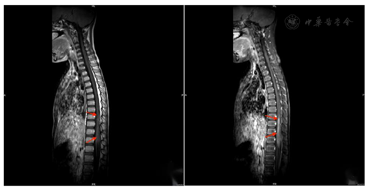

2021年7月16日胸椎MRI:胸7~9椎体水平以下脊髓信号异常,增强后示病灶强化不明显。2021年7月27日胸椎MRI增强(图1)提示胸9~10脊髓及脊髓圆锥内异常信号,出血?2021年8月10日MRI增强(图2)诊断为急性脊髓炎。2021年8月26日MRI增强(图3)提示急性脊髓炎伴脊神经炎,较前有所好转。2021年12月20日胸椎MRI增强(图4)提示急性脊髓炎伴脊神经炎,较2021年8月26日范围稍缩小。